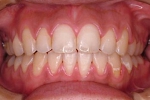

CASE2

↓前歯の歯並びを きれいに治したい。

(35歳/女性)

|||||||||

概要・担当医コメント:叢生・審美障害↑

動的治療期間13ヶ月(12回)/非抜歯/費用概算:55万円

上は固定式のブラケット矯正で,下は患者様ご自身が着脱するマウスピース矯正の治療を行いました.治療結果には大変満足されているそうです.